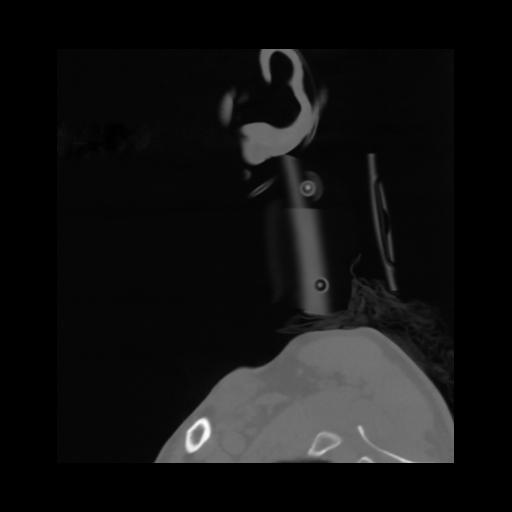

14 P.BLANDAS,,Sagittal,2.000,P.BLANDAS,Sagittal,